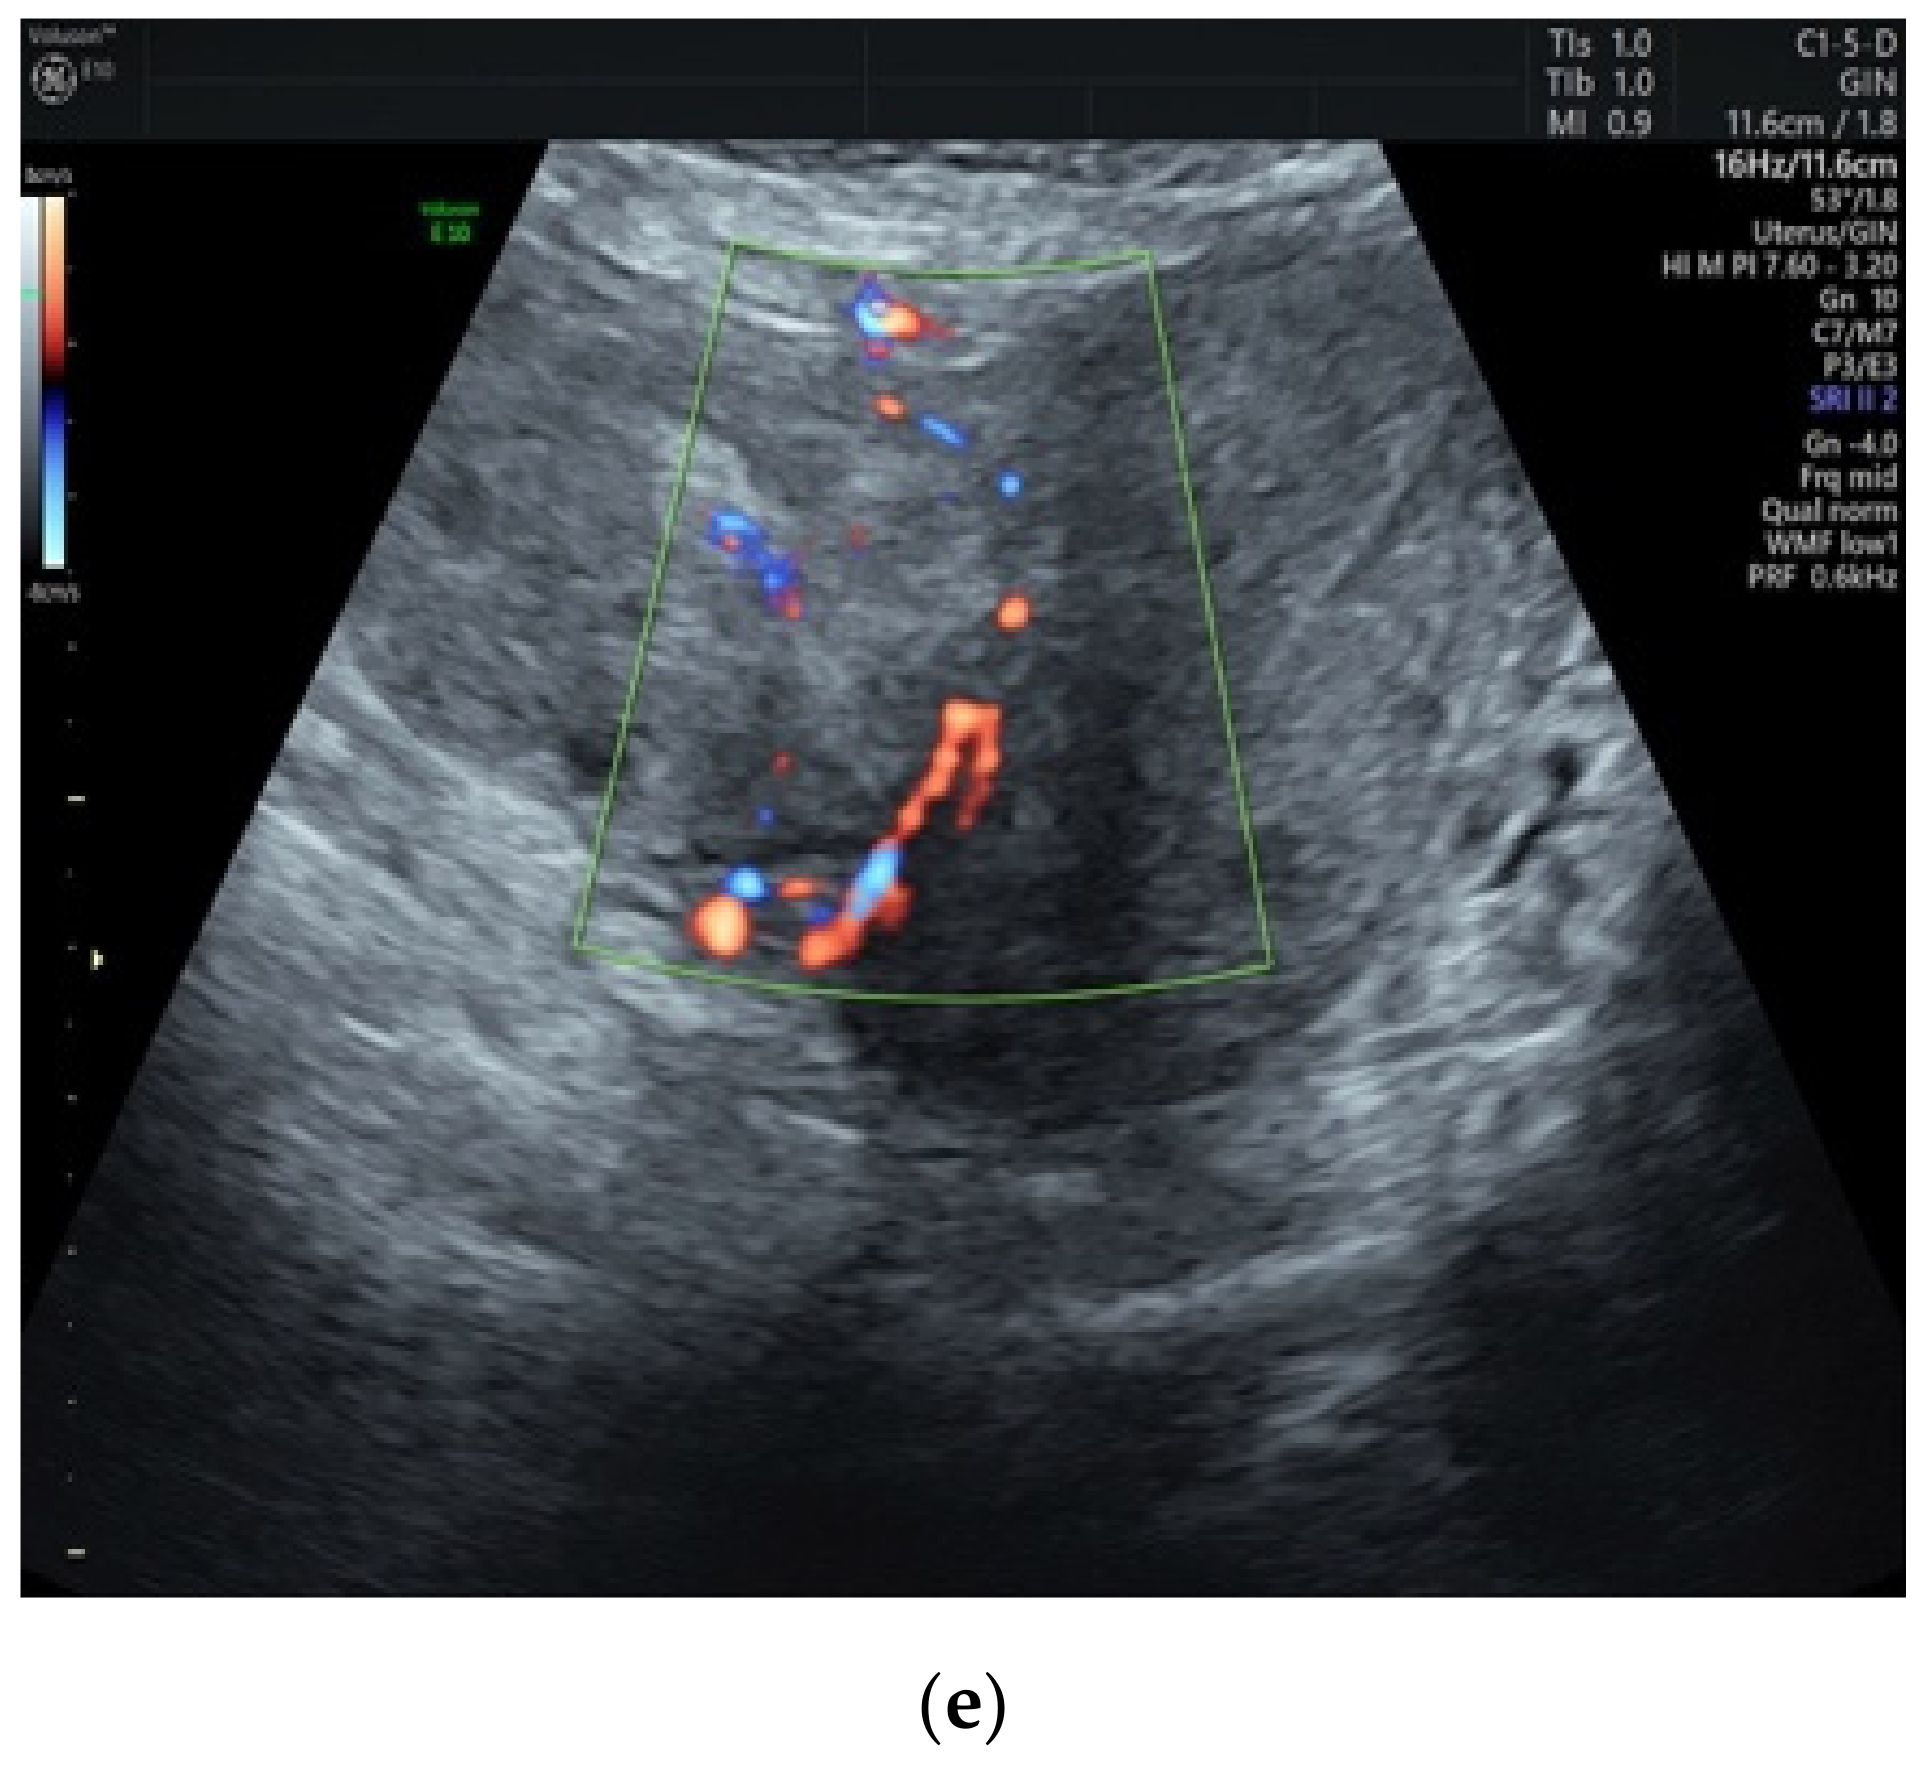

3.1. Preoperative Assessment

| Pelvic Ultrasound | Magnetic Resonance Imaging | During Surgery |

|